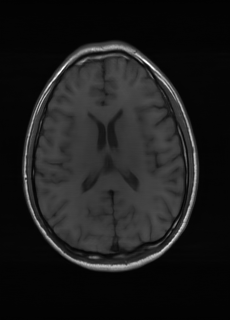

As we observe from the right image in Fig. 2, our BRM, both from MIMO and SISO settings, predicts the performance of dedicated models with a high correlation. We further choose the best three , and perform the last stage of fine-tuning accordingly to (6). A visual evaluation on real data is shown in Fig. 3. For simulated data, please refer to the Supplemental Material section.

Base on the best performing , we perceive that among , , and FLAIR, the results are best when is sampled the most. We suggest that this makes intuitive sense as images provide the best contrast out of the three sequences, which can compensate for the details lost in other images. The same observation can be made on the simulated data, where both and FLAIR show good contrast. When the time setting is changed to non-uniformity, we can see that our search for the best sampling strategy reflects the change. is sampled more as a result of faster acquisition time, while is still sufficiently sampled.

| Sequence | LR | SISO | MIMO | MIMO tuned | GT |

|---|---|---|---|---|---|

(a) 34.38/0.9371

(a) 34.38/0.9371

|

(b) 42.42/0.9883

(b) 42.42/0.9883

|

(c) 44.60/0.9920

(c) 44.60/0.9920

|

(d) 45.50/0.9940

(d) 45.50/0.9940

|

(e) PSNR/SSIM

(e) PSNR/SSIM

|

|

(f) 29.74/0.8903

(f) 29.74/0.8903

|

(g) 36.25/0.9734

(g) 36.25/0.9734

|

(h) 36.42/0.9752

(h) 36.42/0.9752

|

(i) 37.70/0.9832

(i) 37.70/0.9832

|

(j) PSNR/SSIM

(j) PSNR/SSIM

|

|

(k) 39.89/0.9311

(k) 39.89/0.9311

|

(l) 43.94/0.9864

(l) 43.94/0.9864

|

(m) 44.74/0.9883

(m) 44.74/0.9883

|

(n) 45.49/0.9894

(n) 45.49/0.9894

|

(o) PSNR/SSIM

(o) PSNR/SSIM

|